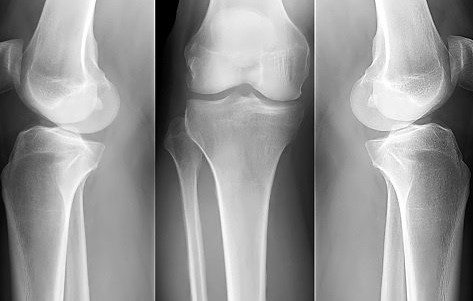

El término significa literalmente hueso poroso. Es una dolencia que reduce la densidad y calidad de los huesos, debilitando el esqueleto y aumentando el riesgo de fractura. Los huesos se vuelven más porosos y frágiles. No hay síntomas hasta que se produce la primera fractura, es una enfermedad silenciosa que puede llegar a causar dependencia.

Alrededor de tres millones de personas padecen esta enfermedad en España y la mayoría de las que la sufren son mujeres, sobre todo, después de la menopausia. Se calcula que a partir de los 50 años dos de cada tres corren riesgo de padecerla, frente a uno de cada cinco hombres. Para las mujeres, el riesgo de fractura de cadera es superior que el riesgo de padecer cáncer de mama, ovarios y útero de forma conjunta. Además, tan solo el 10% de las mujeres mayores con fracturas de fragilidad reciben terapia contra la osteoporosis. A nivel mundial las fracturas por osteoporosis se producen cada tres segundos.